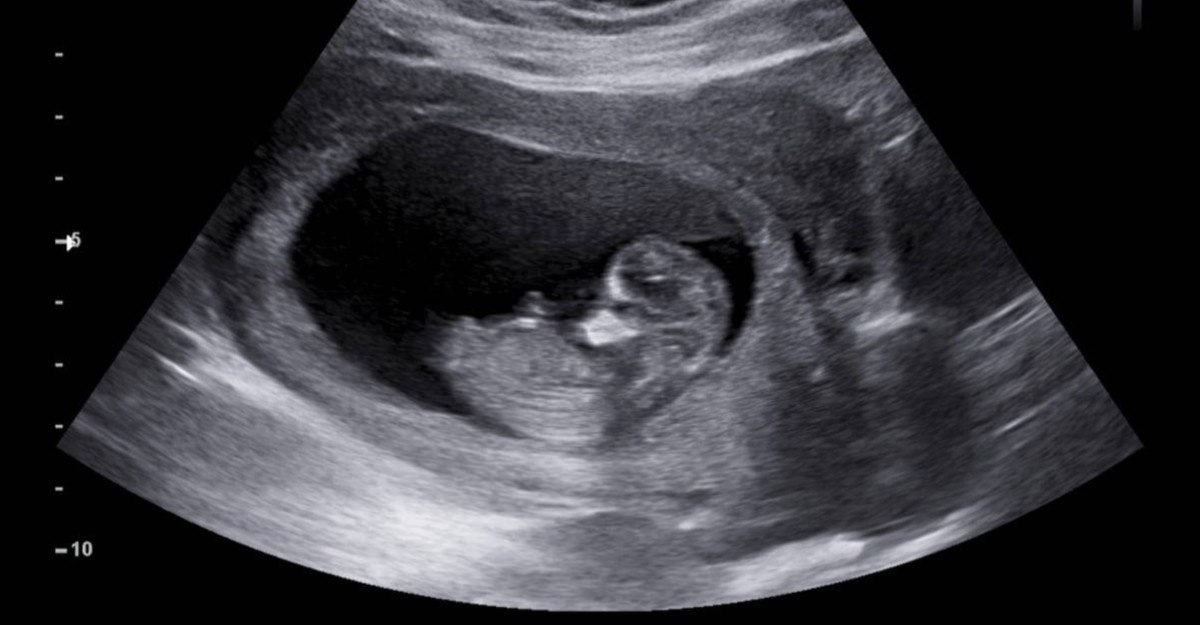

Spinal musküler atrofi, doğumdan önce başlayan ve kas zayıflığının kötüleşmesine neden olan genetik bir rahatsızlıktır.

St. Jude Çocuk Araştırma Hastanesi’ndeki bilim insanları ilk rahim içi tedaviye öncülük etti.

Bugüne kadar tedaviler doğumdan sonra yapılıyordu.

İlacı rahim içi olarak uygulama fikri ebeveynlerden geldi ve doktorlar, anneye ilacı hamileliğinin son 6 haftasında verdi.